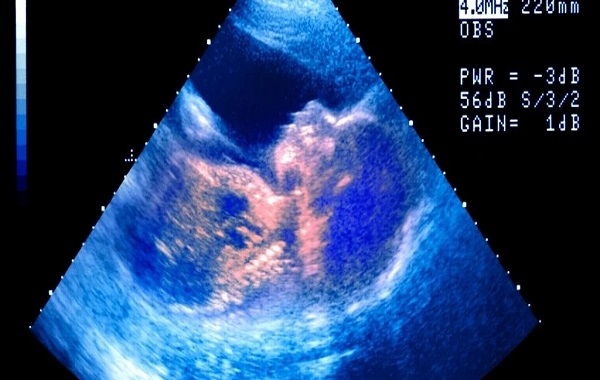

Ultrasound technologies have allowed us to peer inside the uterus and observe fetuses while they’re still developing. For example, a video published in the journal Archives of Disease in Childhood – Fetal and Neonatal Edition in 2005 shows a 33-week fetus making facial expressions that look like crying through an ultrasound profile.

After the researchers gave the fetus a vibration and noise stimulation, it opens its jaw wide, tucks in its chin and lets out three big exhales in a row as its chest rises and its head tilts back, ending with a chin quiver. This movement was seen in 10 fetuses (about 6 percent of the total number of babies scanned).

Reissland’s team has analyzed the development of facial expressions in utero by watching the movements of fetuses in the second and third trimesters through 4D ultrasound imaging – 3D movies of fetal actions.

These facial expressions – including the “cry-face-gestalt” and the “laughter-gestalt” that Reissland and colleagues defined in a paper published in the journal PLOS One in 2011 – may be precursors to the facial expressions used outside the womb.

These preliminary facial expressions develop around 24 to 35 weeks, and their complexity increases with gestational age. These motions are too subtle to be felt by the pregnant parent, Reissland said.